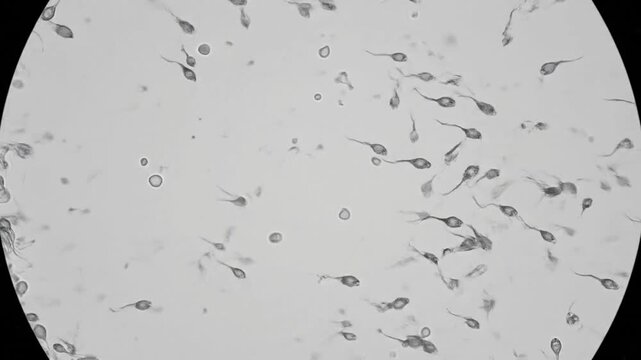

Барлық жерде сперматозоидтардың фотосуреттері